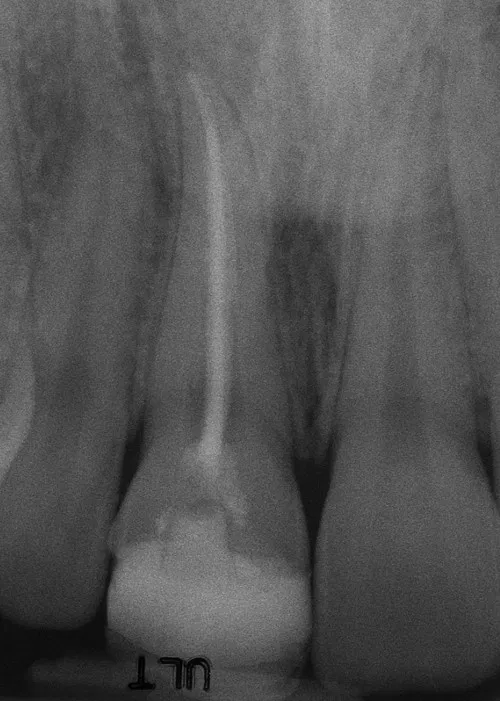

Ceramic Post/Core; Ceramic Crown-Bonded

Before:Â Tooth #8 (upper right central incisor) has a history of trauma and root canal therapy. Re-treatment of the root canal filling was required.

After: Followed by delivery of a custom ceramic post/core foundation, and a bonded all-ceramic full coverage single restoration (crown).